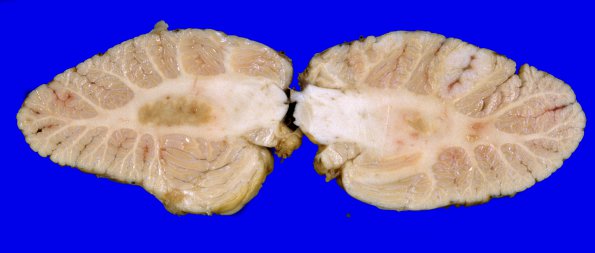

6A2,3 The leptomeninges show focal cloudiness, predominantly over the cerebellar hemispheres (right > left). The cerebellar hemispheres are full and equal in size. Radial sections of the cerebellum show normal foliar architecture; however there are three discrete firm tan lesions; two involving the right cerebellar hemisphere.